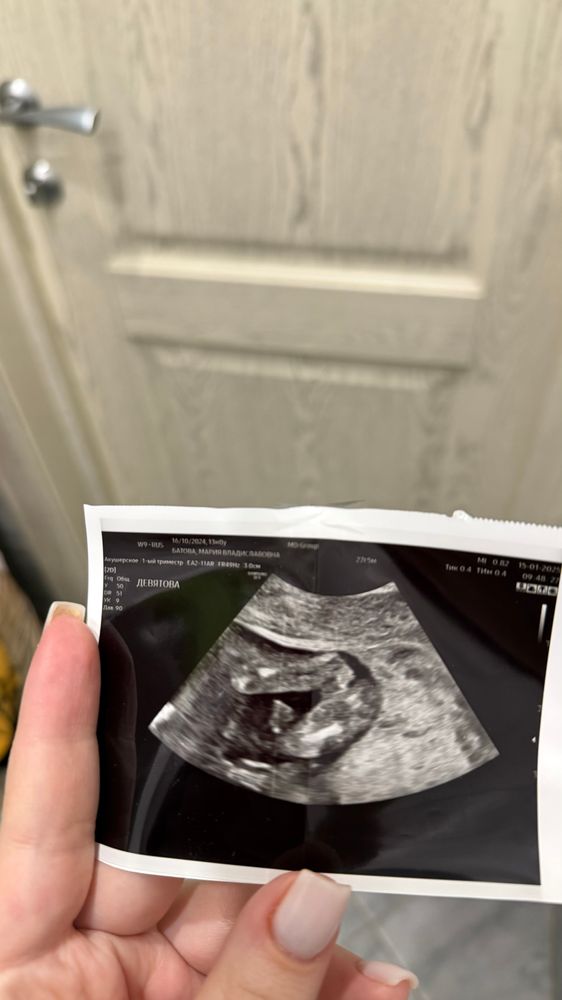

Пол на 12 неделе

На таком сроке это лотерея. Слишком сложно определить, много погрешностией хотите быстро и точно, сдавайте кровь или ждите, пока подрастёт малыш

Мария, на таком сроке очень легко перепутать, слишком маленькое все

Мария, если я не ошибаюсь, до 16 недель у мальчиков и девочек все одинаково :) половой бугорок)

В таком ракурсе нельзя, так бугорок и у тех и у других. К слову мне 2 врача в 12и 13 недель ставили неверный пол ( мальчик). Со средним в 12 недель врач предположил верно ( мальчик)

Катерина, мне предположили девочку, видимо из-за того что ничего не торчит между ножек, но обычно же по наклону полового бугорка смотрят , а не снизу на этом сроке

Мария, да по наклону. Плюсую либо кровь ( но это не 100%), либо ждать 16 недель там уже все видно будет)

Ия, согласна, самый надежный вариант) просто стало интересно, можно ли на таком сроке с этого ракурса сказать что это девочка , из-за того что ничего не торчит

Мария, нет, нельзя

Анастасия, мне предположили девочку из-за того что ничего не торчит между ножек, видимо. А у других я смотрю по наклону бугорка смотрят, а не вид снизу

На таком сроке и у мальчиков, и у девочек все одинаково

По такой фотке пол не скажешь, нужно сбоку смотреть. У них в 12 недель у всех «писюны», только угол отличается) Посмотрите у меня в профиле фотку с узи в 13 недель, как пример

Елизавета, посмотрела) у вас там как раз ракурс сбоку и видно половой бугорок хорошо, а у меня по виду снизу ничего не торчит и врач считает что девочка поэтому

Мария, я бы не была так уверена 🤔 Интересовалась этой темой после первого узи и нигде не нашла информацию, как кроме вида сбоку можно определить пол на сроке до 15 недель